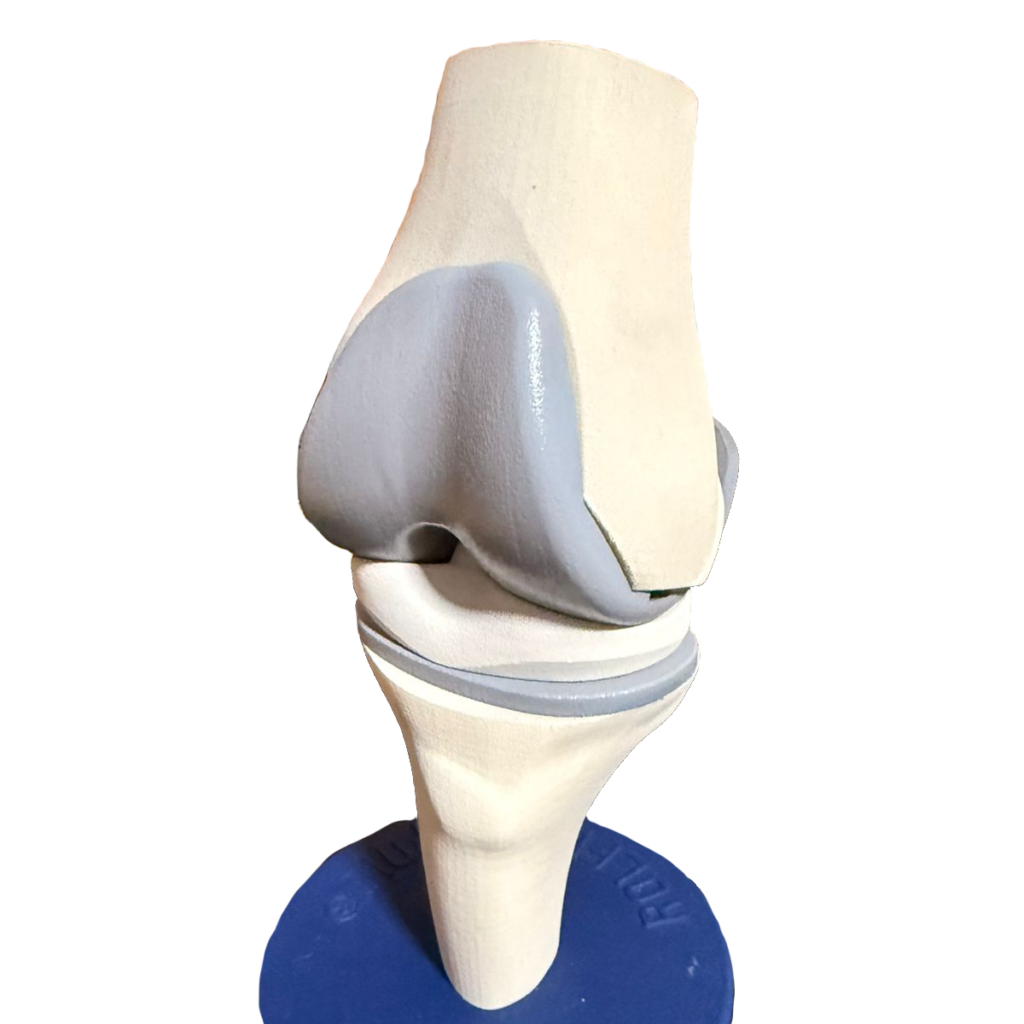

Rodilla

Conoce el reemplazo protésico de rodilla.

La prótesis de rodilla no sustituye a la rodilla original. Remueve una fina capa de cartílago dañado y coloca una cobertura metálica en los huesos con un inserto de polietileno intermedio para lograr un movimiento armónico.